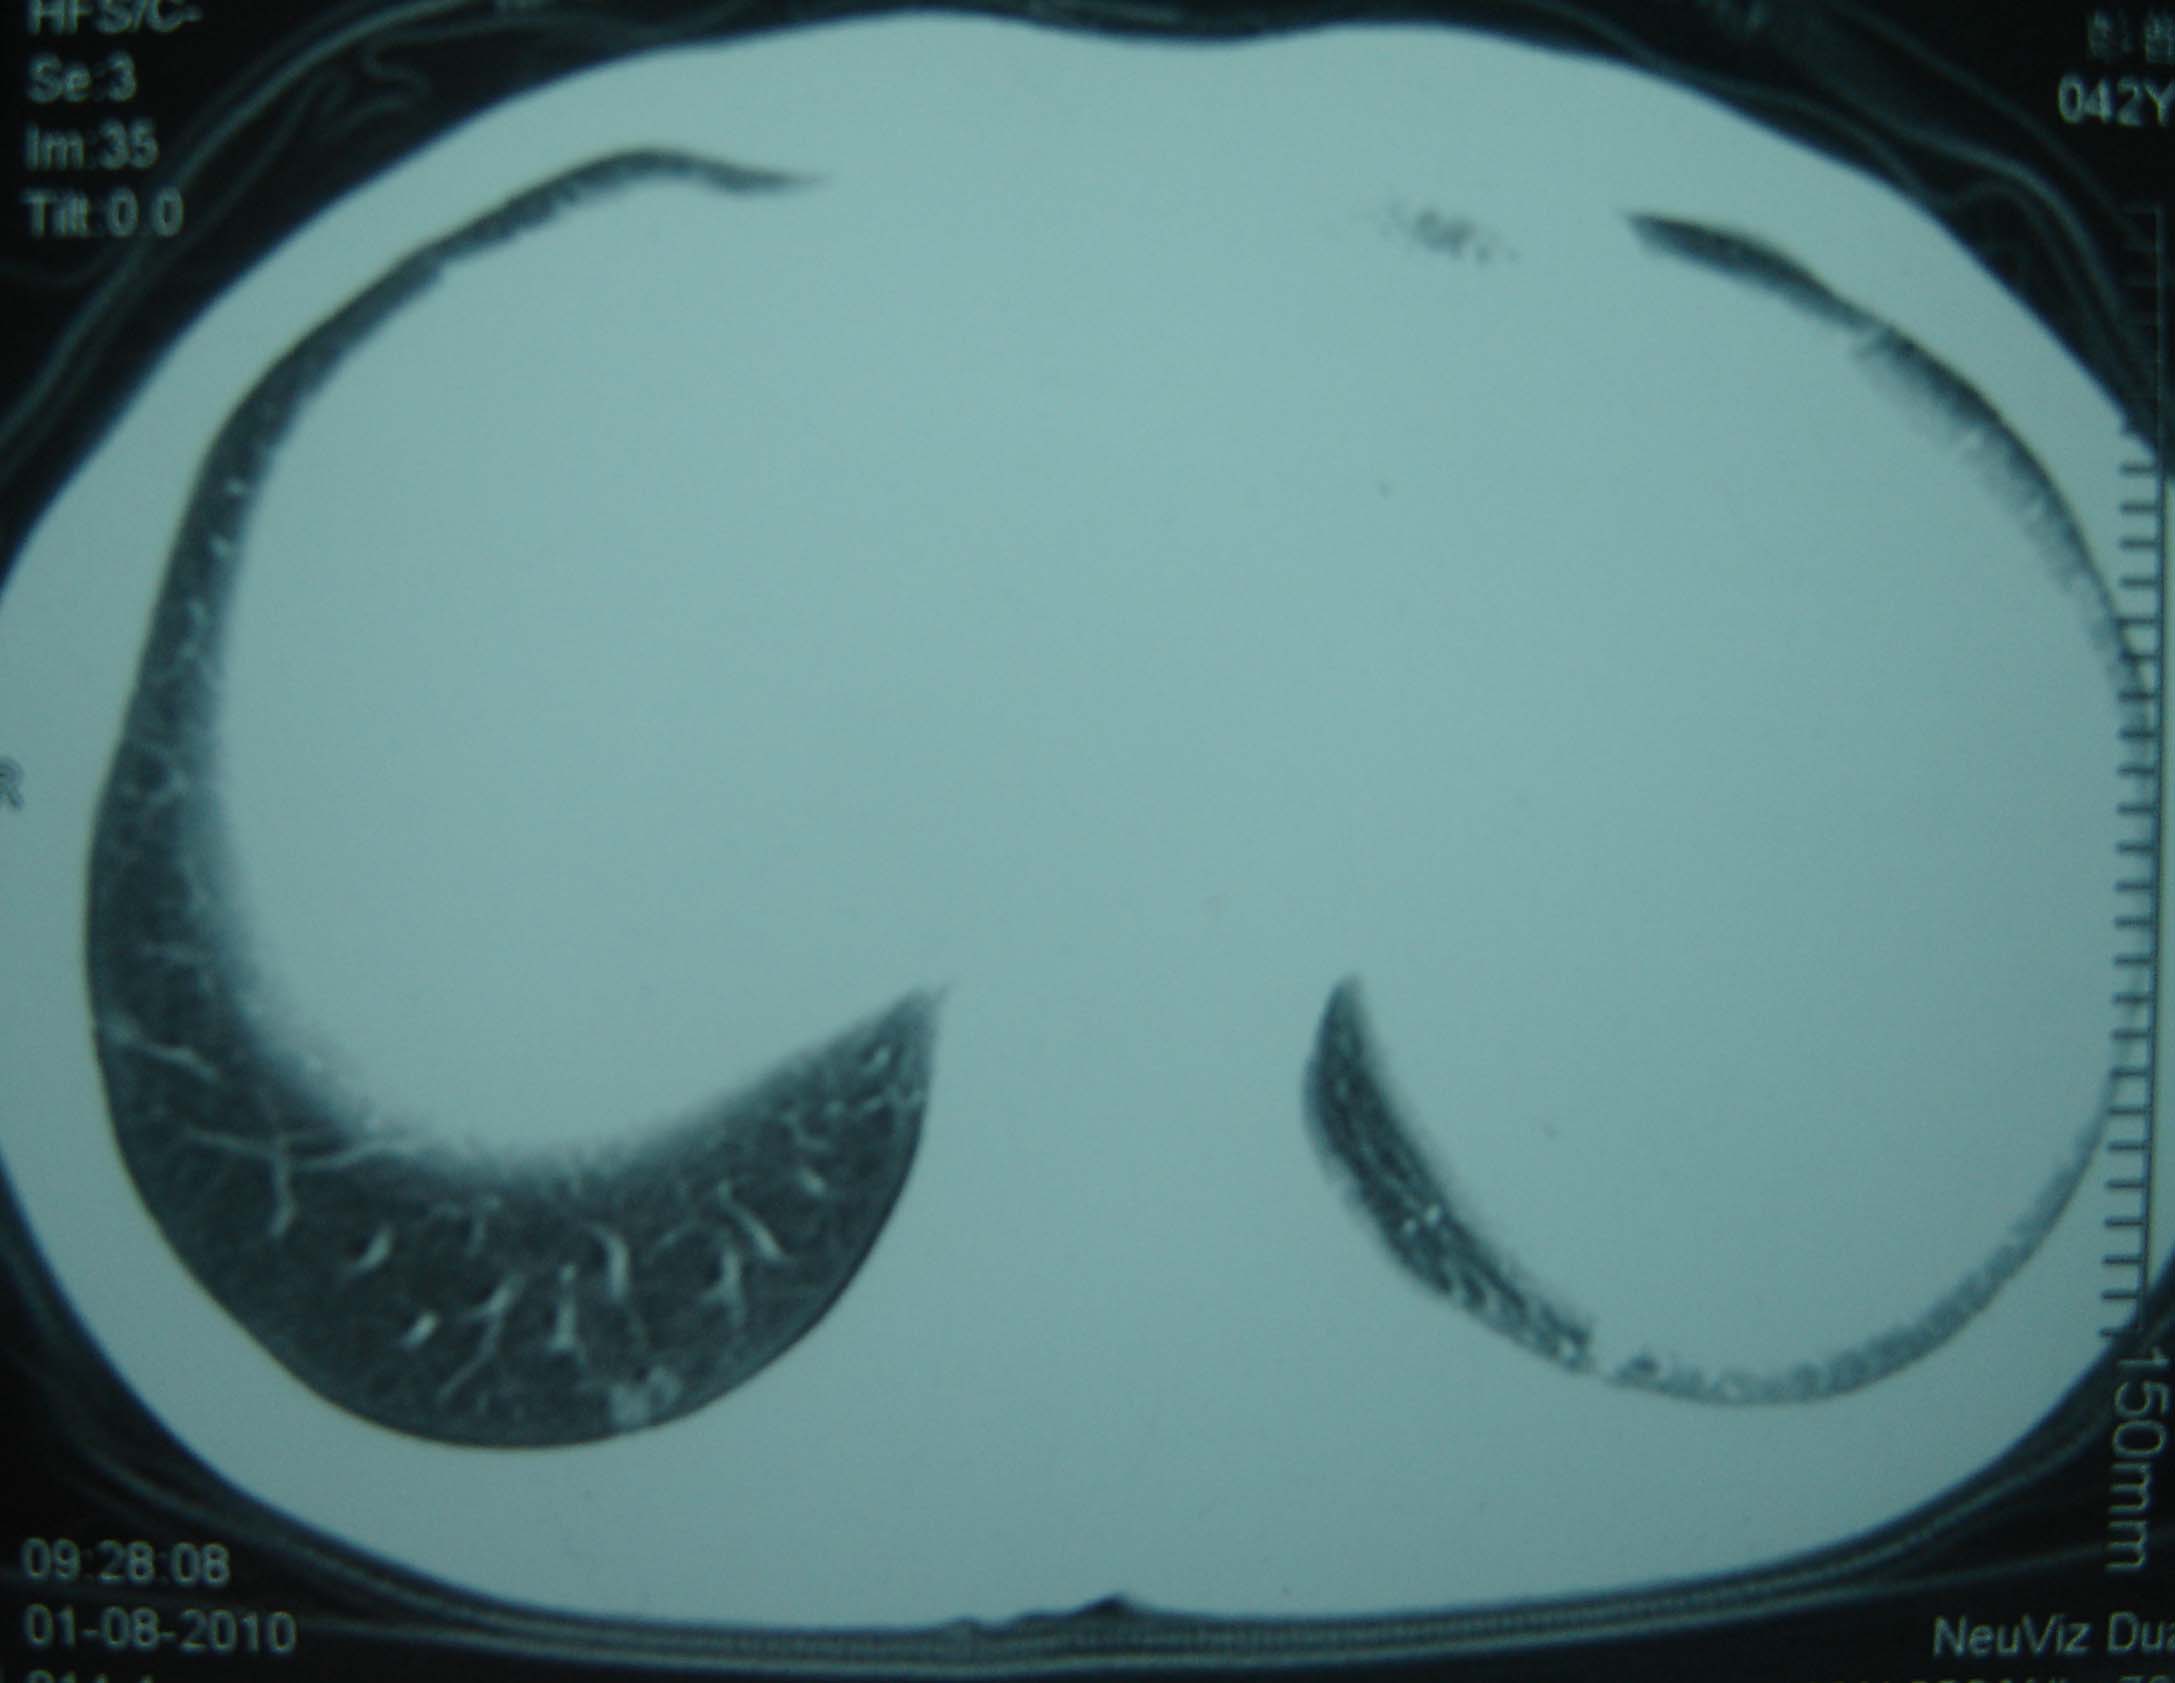

标题: CT25321:两肺多发结节 请会诊 [打印本页]

标题: CT25321:两肺多发结节 请会诊

男 、43岁,咳嗽胸痛,装修工,平时接触粉尘较多,有吸烟史10多年,纤维支气管镜检查未发现异常,胃镜、腹部b超检查亦未发现异常,颈部淋巴结活检未发现肿瘤细胞。

1)考虑双肺及胸膜多发性转移瘤。2)肺气肿。